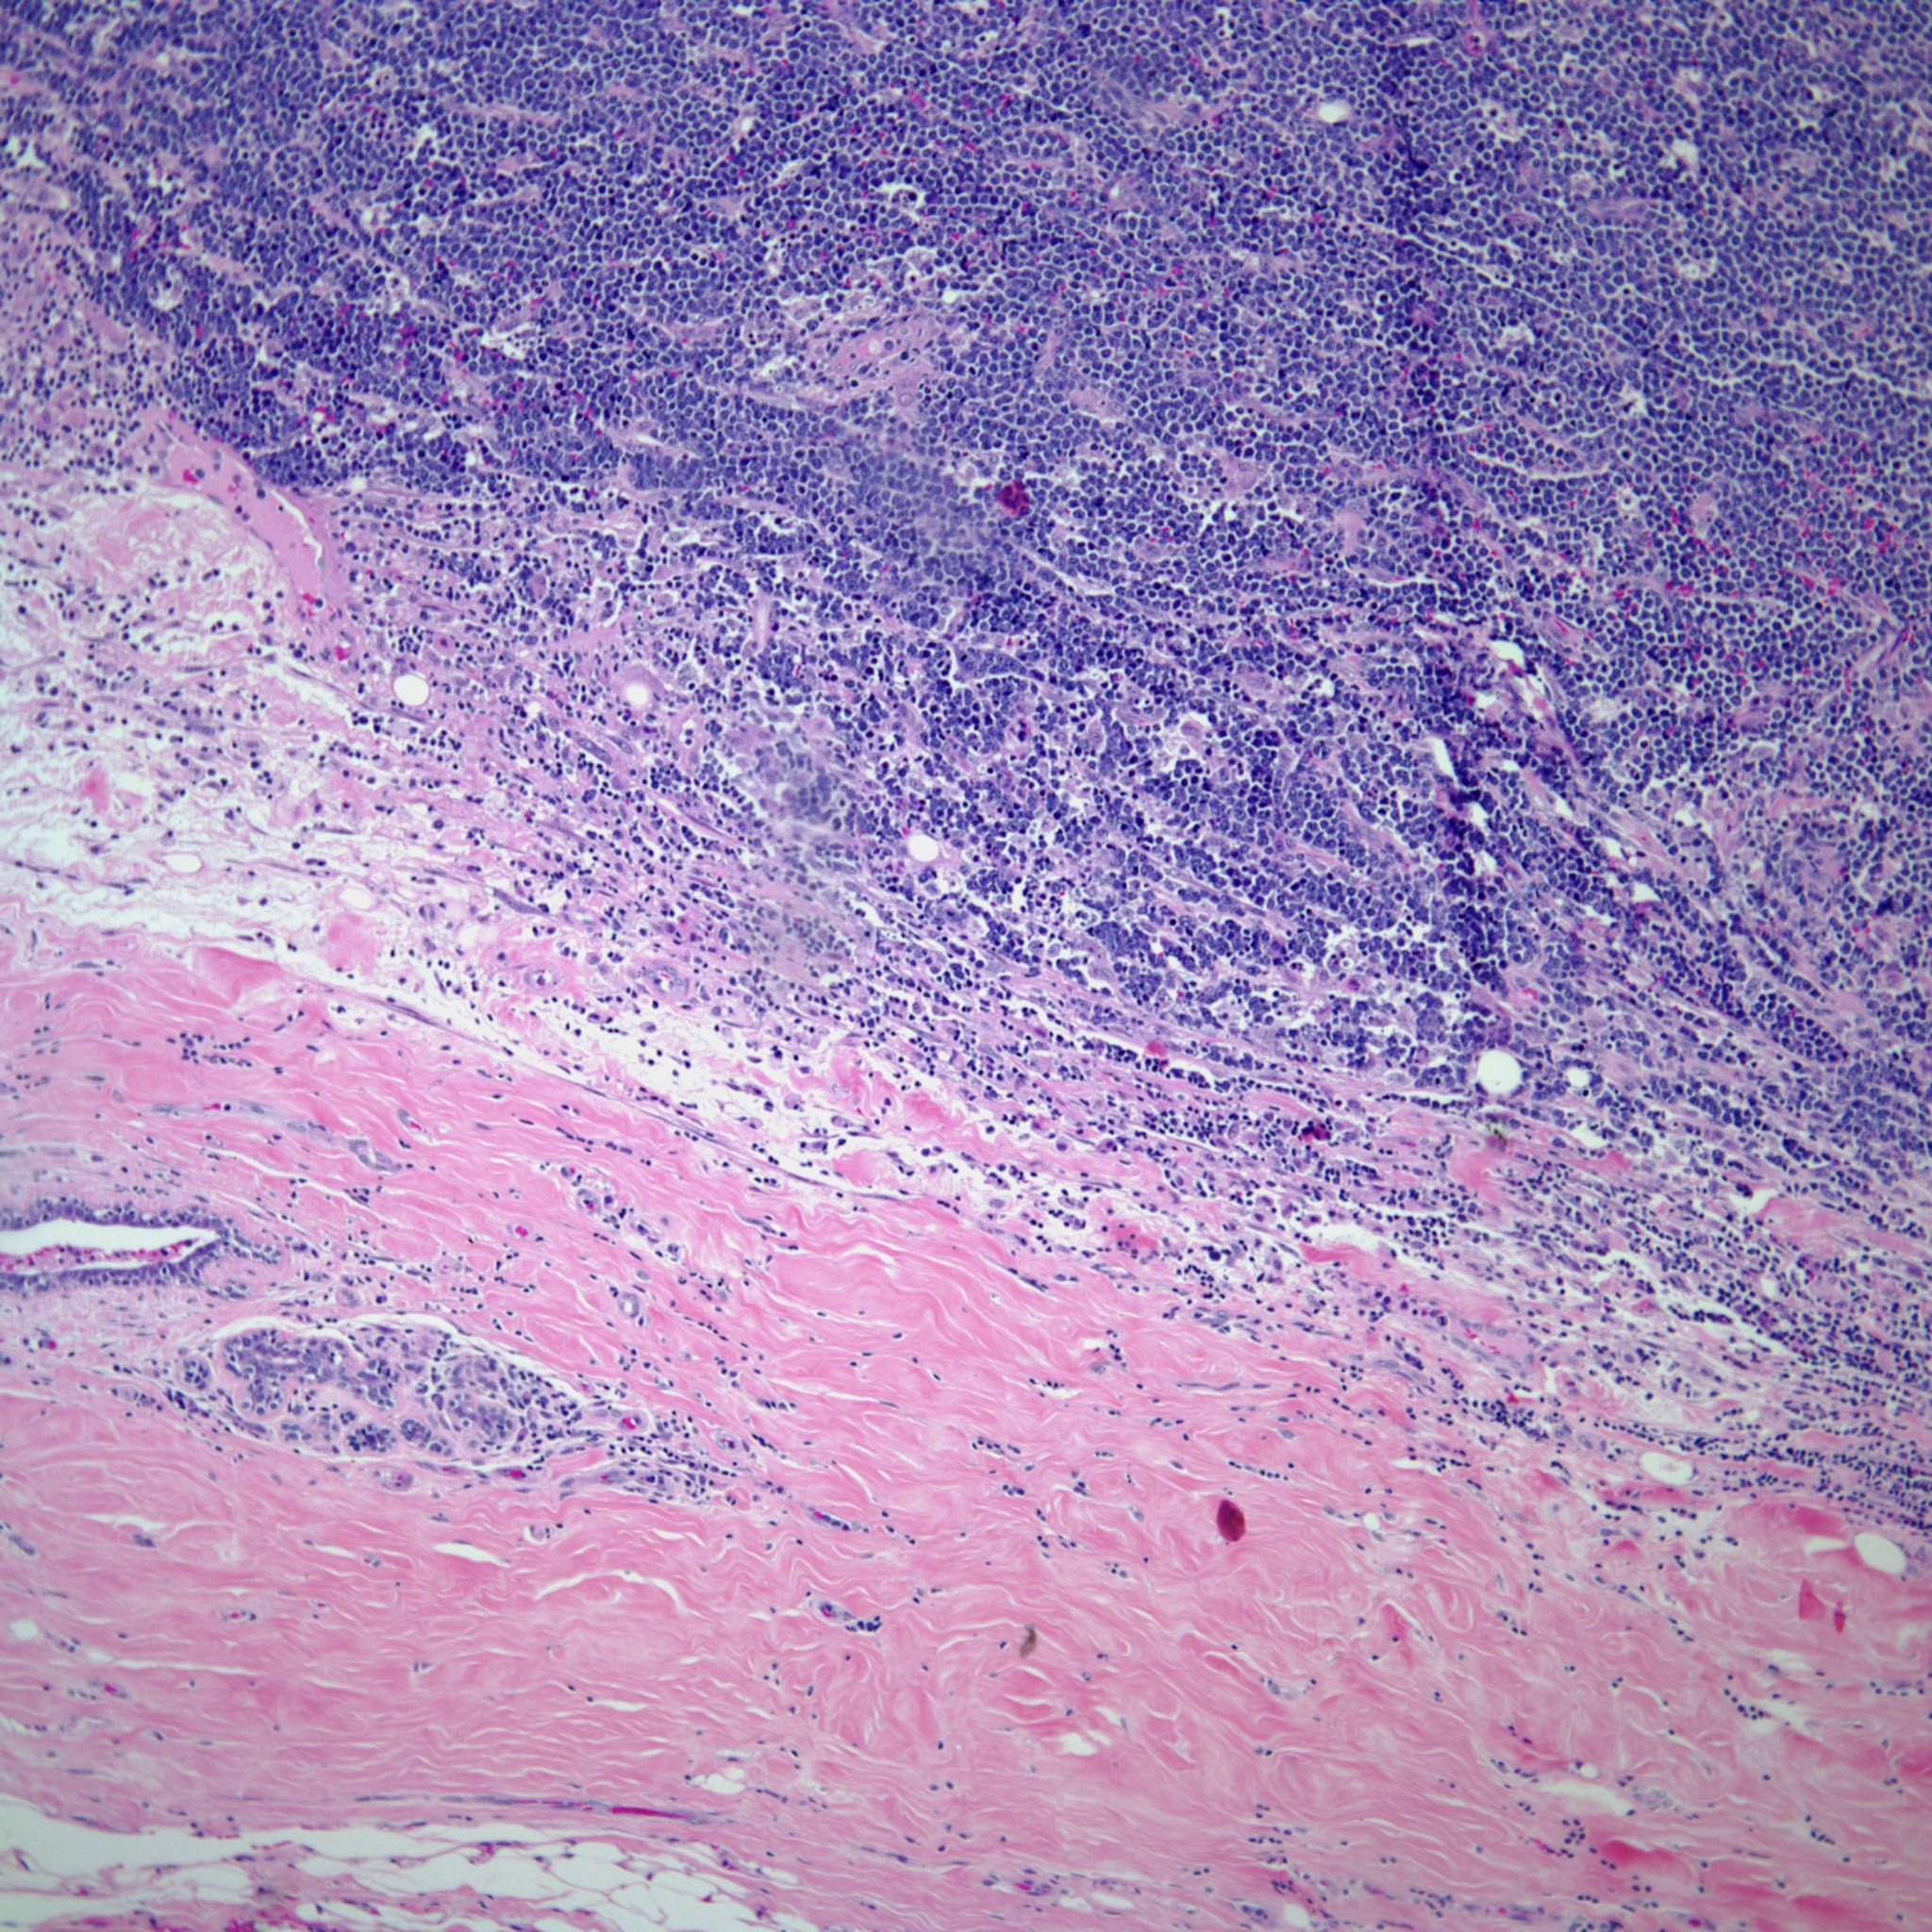

A breast mass is found in a 46-year-old woman, and a biopsy is obtained. What is your diagnosis?